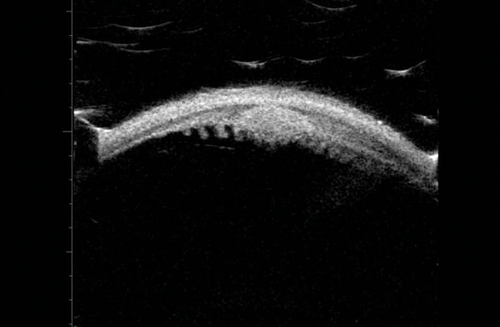

Figure 9: Large irido-ciliary cyst causing anterior bowing of the peripheral iris.

Iris cysts

UBM is the gold standard when evaluating and following up irido-ciliary cysts. These are visualised as thin walled echolucent lesions (Figure 9). Figure 10 shows large irido-ciliary cysts causing IOL displacement. Figure 11 shows a non-axial UBM exploring a lesion that was initially referred as a melanoma. This was a pseudophakic eye with a lens remnant. A clear demarcation can be seen between the lens fragment and the iris, as apposed to melanomas, which are more homogenous (as in Figure 7).